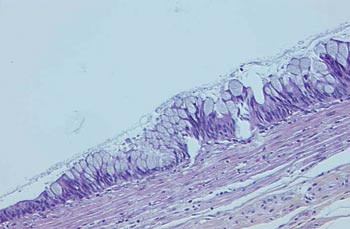

Mikroskopisk vurdering (fig 2) viste appendix med dilatert, slimfylt lumen og enkelte «slimsjøer» i veggen. Lumen var kledd med enradet epitel, noen steder med flerradige mucinholdige celler. Cellene viste lav til moderat grad av atypi. Det ble ikke påvist infiltrasjon i appendixveggen ved rutinefargede snitt (hematoksylin-eosin-safran-farging) eller ved immunhistokjemisk undersøkelse (cytokeratiner). Funn av «slimsjøer» i blindtarmens vegg ble betraktet som mekanisk forårsaket av økt intraluminalt trykk. I mucosa fantes lettgradig granulocyttinfiltrasjon, likeså i serosa. Det var frie reseksjonsrender.

På bakgrunn av de beskrevne funn ble det konkludert med diagnosen «mucinøst cystadenom med moderat atypi i appendix».

Mucinøse cystadenomer har histologisk mucinproduserende epitel av kubisk eller sylindrisk type, med mønster varierende fra enradet kubisk epitel til veldifferensierte, papillære formasjoner. Grad av atypi varierer, og mitoser forekommer (5, 6).